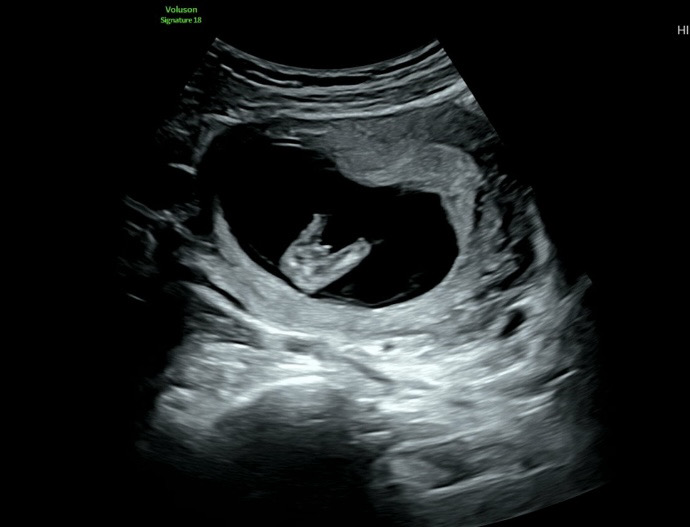

12주에 성별...이거 빼박일까요..ㅋㅋㅋ

저기보이는게 곧휴..... 맞겠죠..??? 첫째는 딸이라 아들이라도 상관없긴한데 12주에 이렇게 보이는게 맞나 싶어서욬ㅋㅋㅋ

네ㅎㅎ🌶️